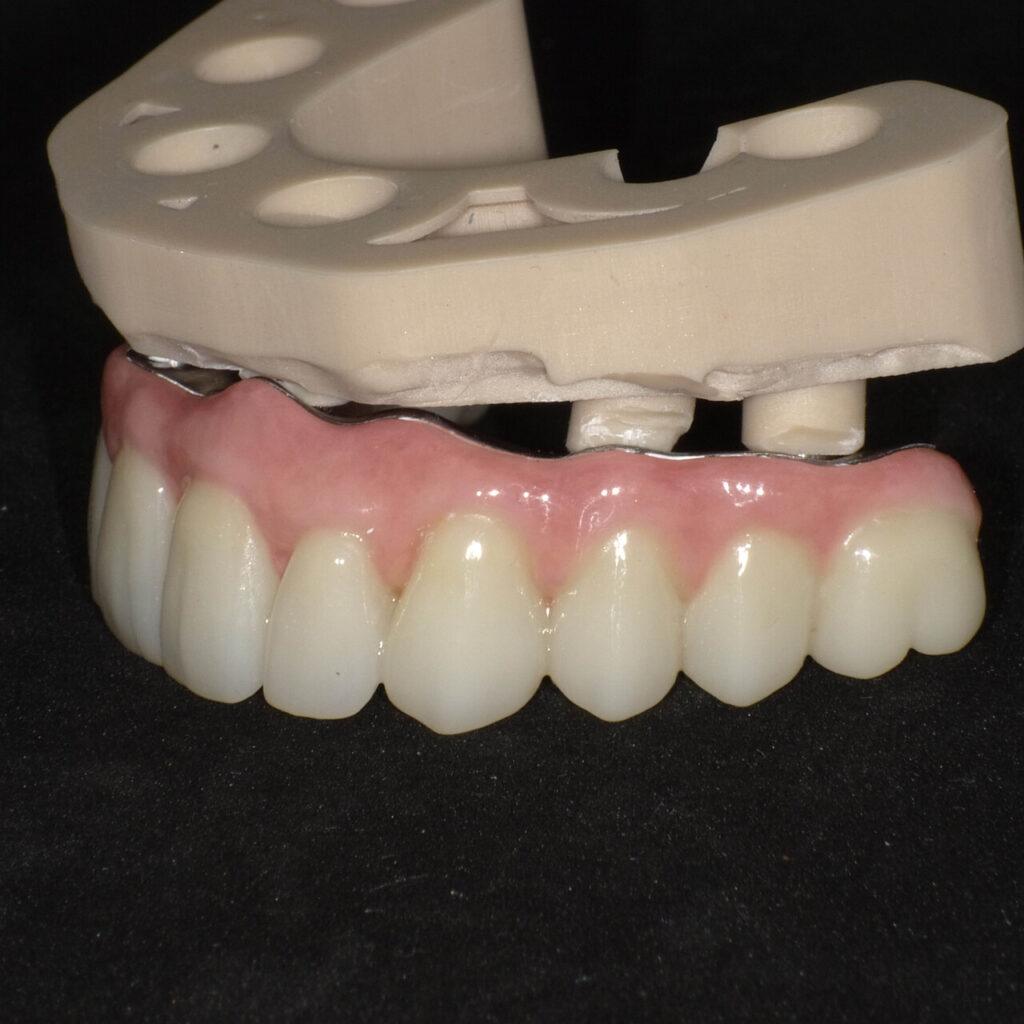

Zabieg 1-3hPo okresie gojenia (4-6 mies.) zakładamy stałe zęby. Wyglądają i działają jak naturalne. Jesz co chcesz, uśmiechasz się bez skrępowania. Nie chodzisz bez zębów ani jednego dnia.

Efekt na lataStałe zęby na 6 implantach zamiast ruchomej protezy. Wszystko zaplanowane z góry, bez niespodzianek.

Brakuje wszystkich zębów → SAFE ARCH (stałe zęby na 6 implantach)